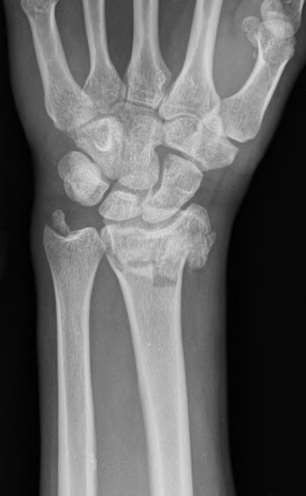

A 35-year-old woman reports wrist pain after a fall onto an outstretched hand. On exam, she has focal tenderness over the wrist snuffbox. A radiograph and CT image are shown in Figures A and B. What is the proper treatment of her injury?